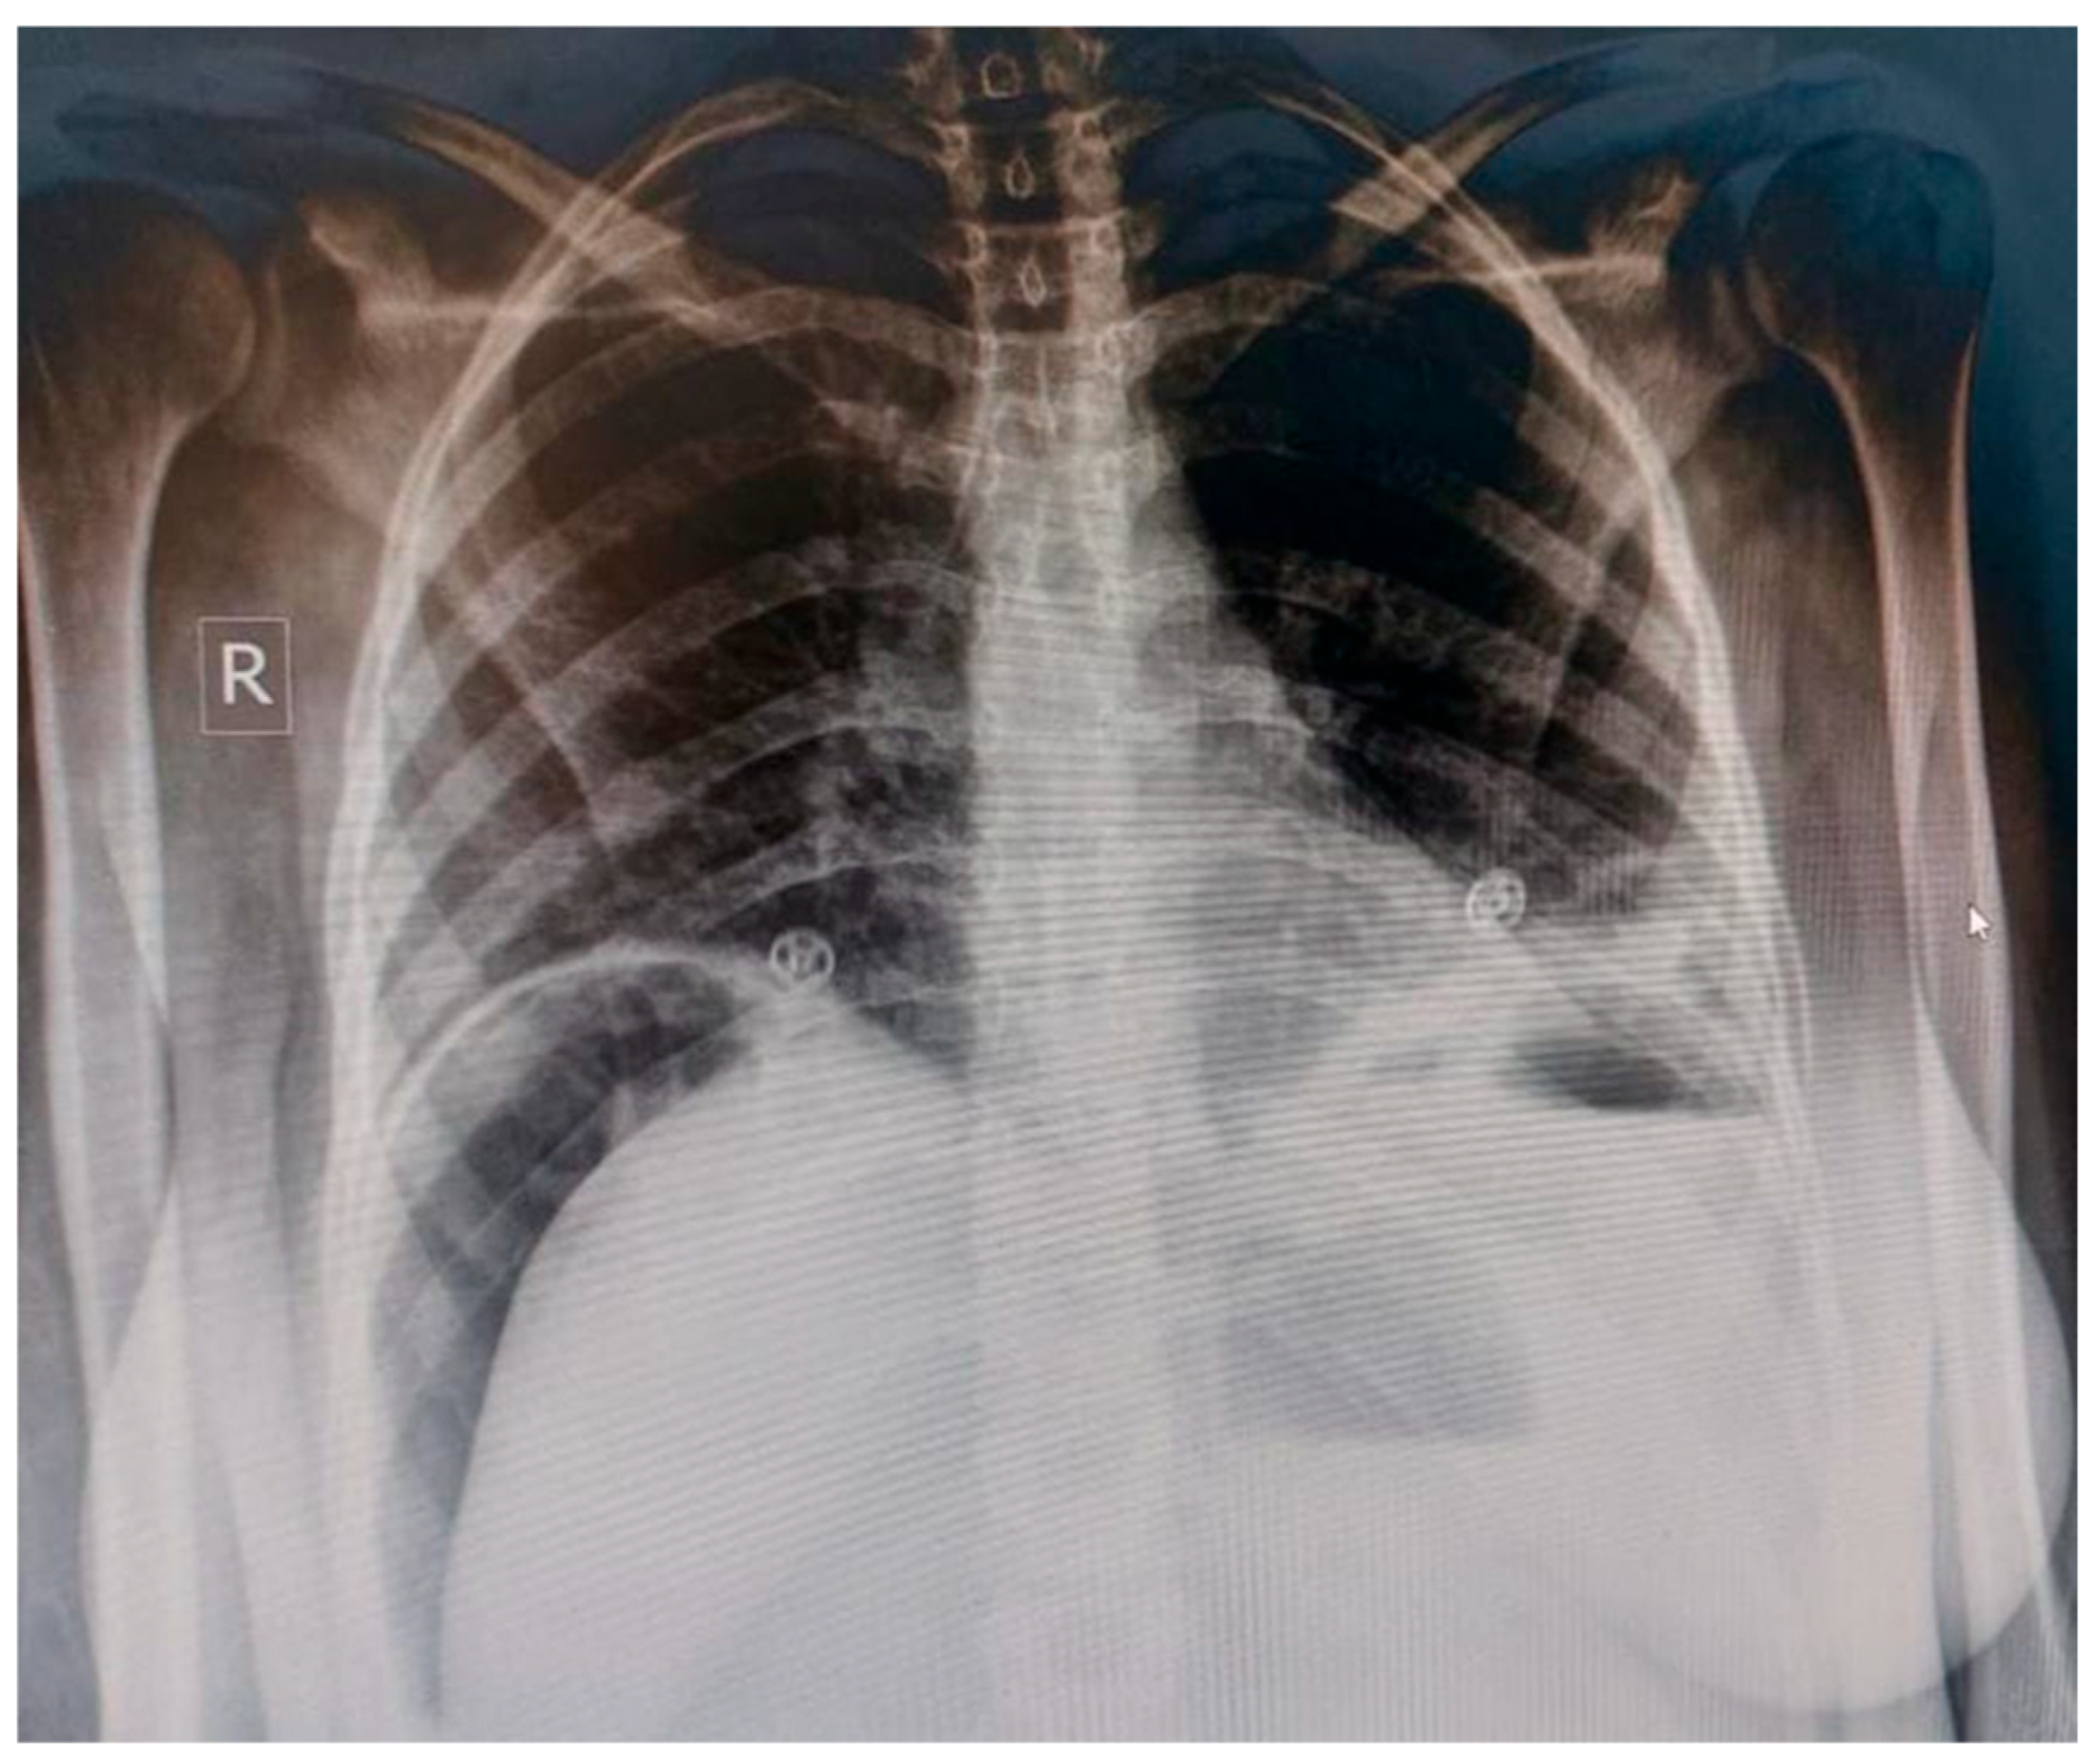

| Imaging | Suspicion for intra-abdominal pathology | Abdominal X-ray showing pneumoperitoneum, dilated bowel loops, and subcutaneous edema | Emergency surgical consultation |